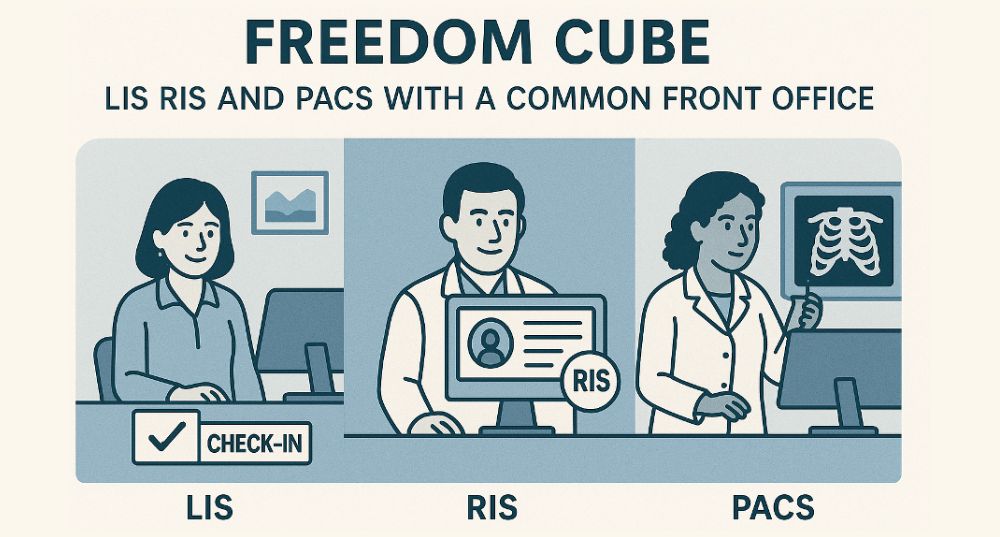

Innowave Healthcare is a leading Indian MedTech software company revolutionizing diagnostic imaging since 2013. We offer AI-powered PACS-RIS, teleradiology, tele-ophthalmology, and workflow solutions trusted by diagnostic centers and hospitals across India, Southeast Asia, West Asia, Africa, and North America. Our flagship Freedom Nano platform is a cost-effective, multi-specialty workflow system supporting radiology, cardiology, ophthalmology, and more. We empower clinicians with fast, accurate, and connected diagnostics—even in remote locations. At Innowave, we innovate to make healthcare smarter, more accessible, and truly transformative.